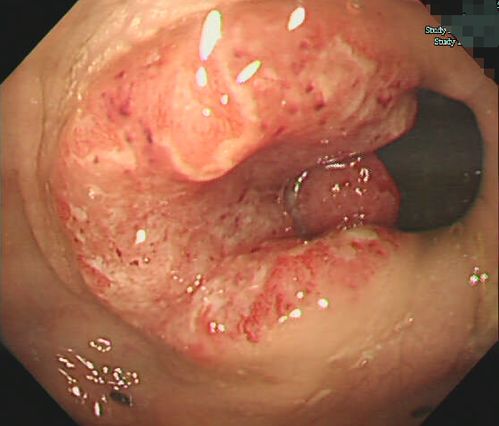

有案例显示可乐在特定条件下被用于溶解某些肠道堵塞物,但这绝对不意味着它能溶解恶性肿瘤。目前,临床证据并不支持可乐具有溶解恶性肿瘤的功效。对于这类传闻,我们应该保持警惕,避免误导他人或自己。